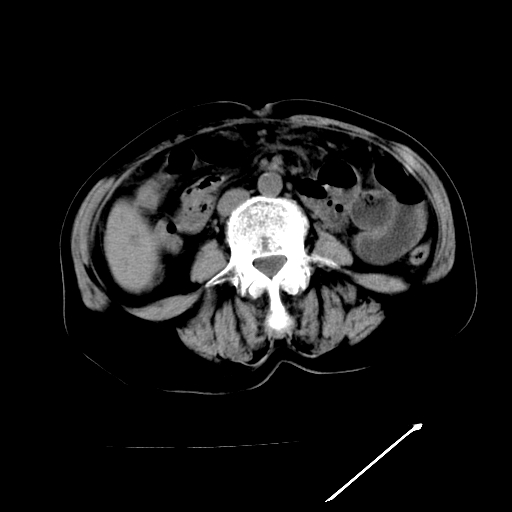

以下是引用卜一在2009-4-7 5:06:00的发言:[br]左右肝内胆管结石伴扩张合并胆系感染;不除外胆管细胞癌可能。支持! [br] [br]

以下是引用随光逐影在2009-4-7 8:21:00的发言:[br]肝内外胆管多发性结石并肝内外胆管扩张;胆系感染。